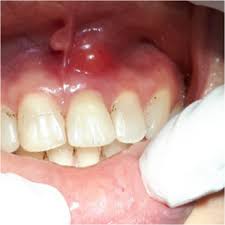

Absceso Periapical Crónico

Un absceso periapical crónico es una infección prolongada en la punta de la raíz del diente que forma una bolsa de pus.

Los pacientes pueden tener dolor leve o no tener síntomas, pero notar una fístula en la encía.

El tratamiento incluye un tratamiento de conducto y, en algunos casos, una cirugía apical. Es crucial tratarlo para evitar la propagación de la infección.